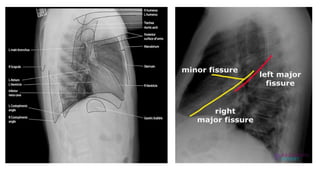

● Fields and fissures

Lateral chest radiograph reveals

complete collapse of the right upper

lobe with opacity anterior to the right

major fissure